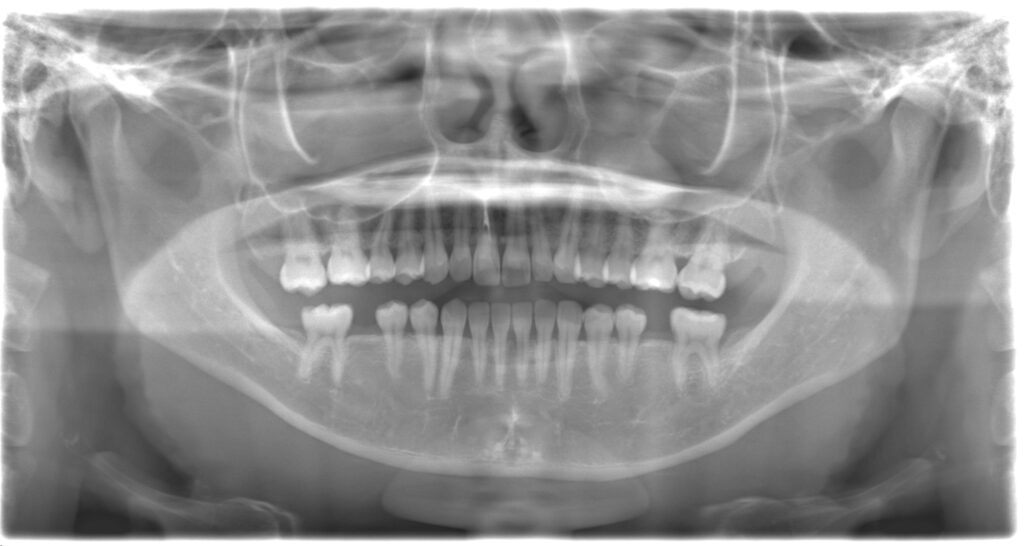

| 備考 | 右下6番の近心根と分岐部が歯根破折により腫れて痛みがあるとのことで来院されました。 抜歯と同時にインプラントを埋入する抜歯即時インプラントを行い、骨欠損部には骨補填材を填入しGBR(骨造成)を行いました。右下6番の治療中に右下7番の近心に虫歯があったため、銀歯を除去し、セラミックインレー修復を行いました。 見た目も綺麗になり、腫れることもなくなったため、患者様はとても満足されていました。 現在はエアフロークリーニングを行いながら経過をみています。 体調を崩した時、疲れた時などに腫れたり膿が出る歯がある方は一度ご相談ください。 |